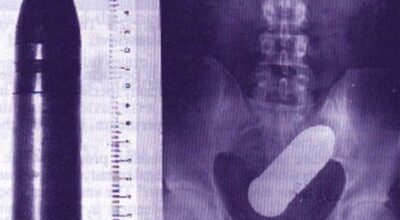

Esta recopilación de imágenes recoge alguna de las situaciones más estrambóticas que se han podido dar en una sala de rayos X. Todas ellas tienen algo en común: Son objetos extraños para el cuerpo humano que, de alguna manera han encontrado una vía de entrada, pero se han perdido a la hora de encontrar la de salida.

Muñecas de juguete descabezadas, botellas, armas, frascos, botes de plástico, teléfonos y hasta una cinta de casete pueden encontrarse en esa suerte de “punto limpio” al que ha quedado reducido el interior de los afectados.

No sabemos, ni juzgamos, la forma o los motivos por los que terminaron atrapados en dichas partes del cuerpo, pero estamos convencidos de que algún doctor estuvo al borde de la carcajada cuando se encontró con casos tan llamativos e inverosímiles como estos ¡Ver para creer!